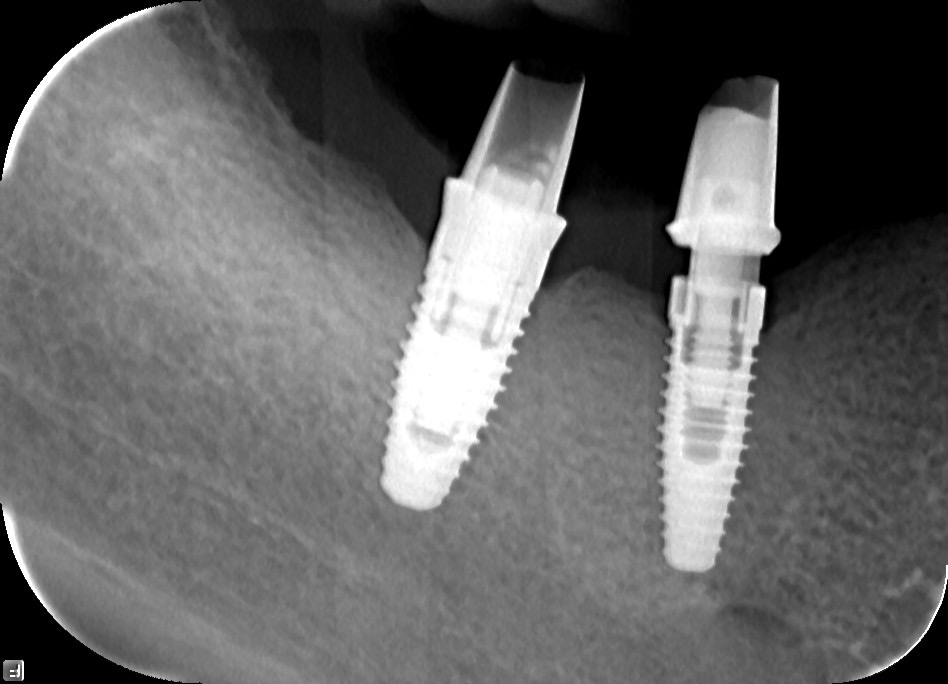

Dental implants are titanium screws surgically placed into the jawbone to serve as artificial tooth roots. Crowns, bridges, or dentures are then mounted on them, creating a functional and aesthetic replacement for missing teeth. Titanium is a biocompatible material that fuses with the bone through a process called osseointegration, making the implant a solid anchor for the prosthetic restoration.

Diagnostics and planning: a thorough analysis of the bone, teeth, and soft tissues using digital radiography. Based on the findings, a precise treatment plan is developed with optimal implant positioning.

Osseointegration: a period of 3 to 6 months during which the implant fuses with the bone. In the meantime the patient wears a temporary restoration.